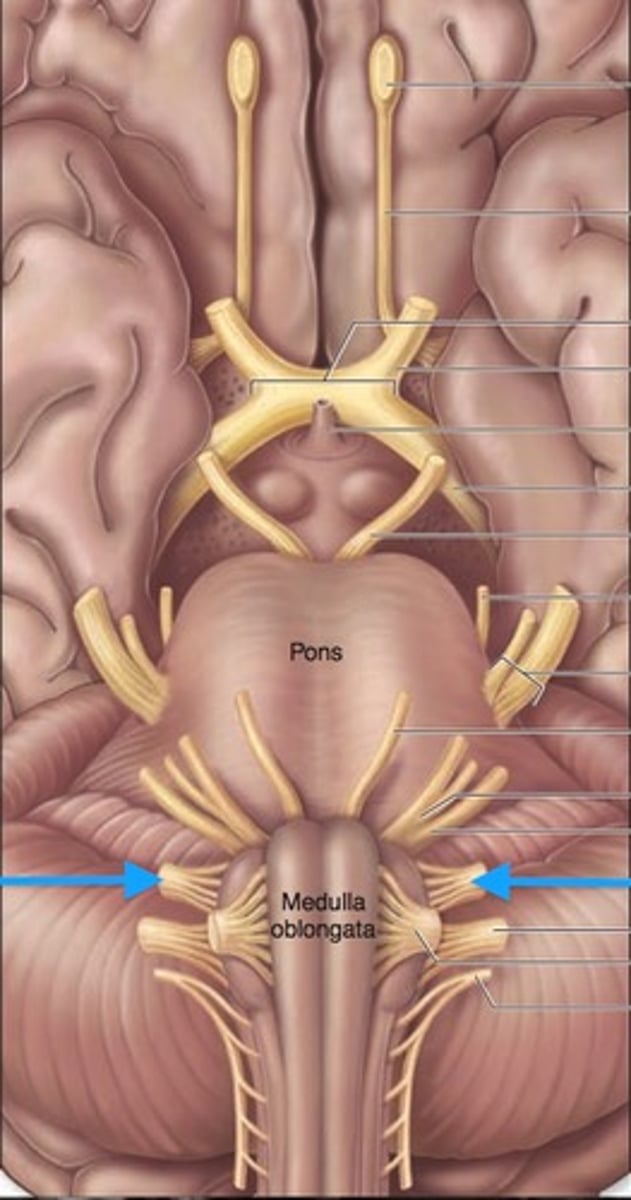

medulla oblongata

most inferior part of the brain stem; regulates breathing, heart rate, & blood pressure

the 'olives'

oval-shaped structures located on the anterior surface of the medulla, lateral to the pyramids

vestibulocochlear nerve

receives sensory input & sends motor output to cochlea of the inner ear for hearing

glossopharyngeal nerve

relays sensory & motor impulses related to taste, swallowing & deglutition

vagus nerves

processes input/output of pharynx, larynx & thoracic/abdominal viscera

accessory nerves

controls swallowing via vagus nerves

hypoglossal nerves

controls tongue movement; speech

pons

center structure of the brain stem, located between the midbrain and the medulla oblongata

trigeminal nerves

regulates sensory input from head & face, governs chewing

abducens nerves

controls eyeball movement, particularly abduction (outward gaze)

facial nerves

regulates facial movements, saliva, tears

vestibulocochlear nerves

the vestibular and cochlear nuclei in the pons are involved in balancing and hearing